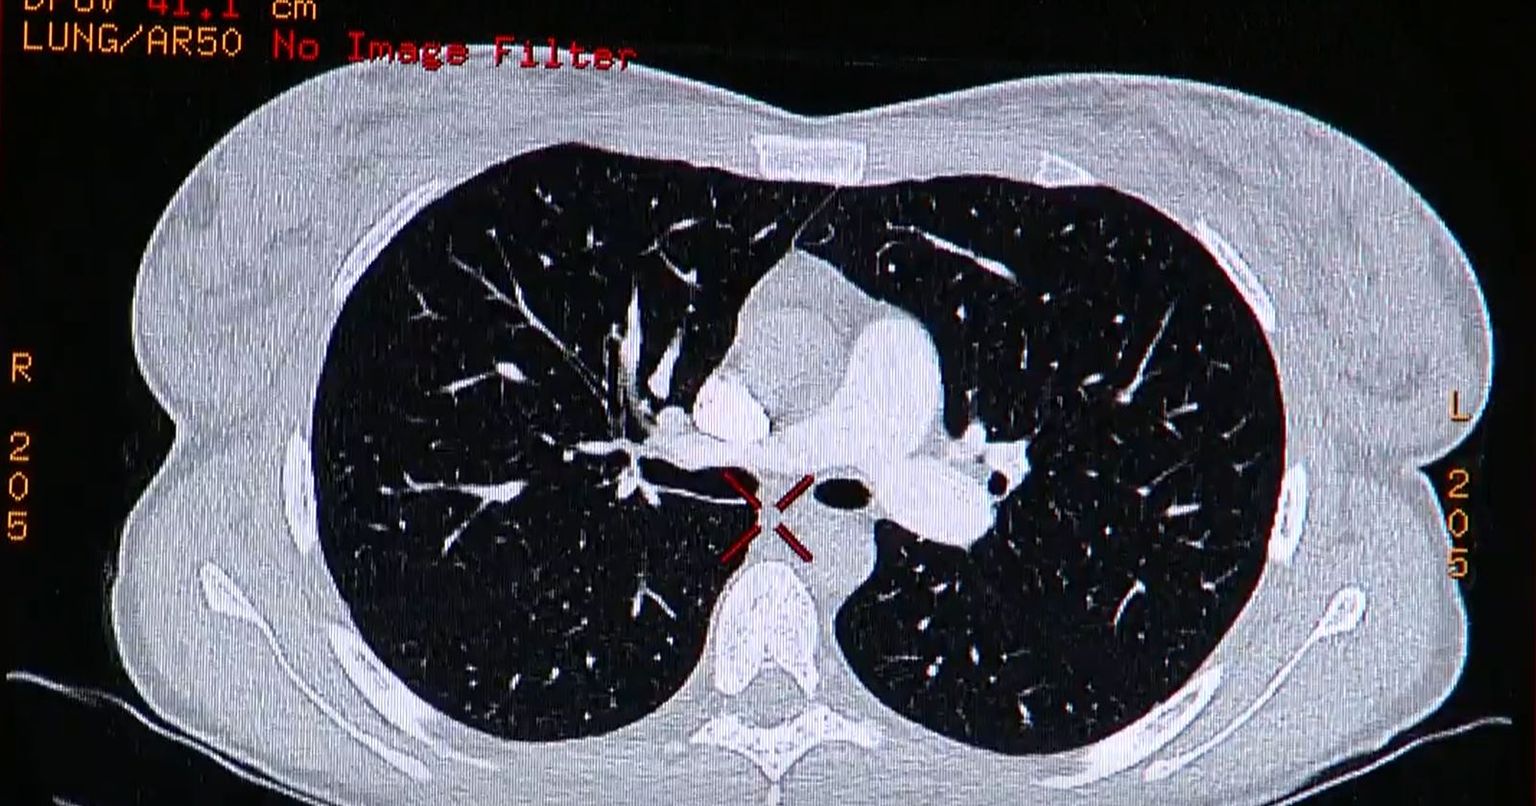

• Rano otkrivanje karcinoma - 3 Foto: DNEVNIK.hr

• Rano otkrivanje karcinoma - 4 Foto: DNEVNIK.hr